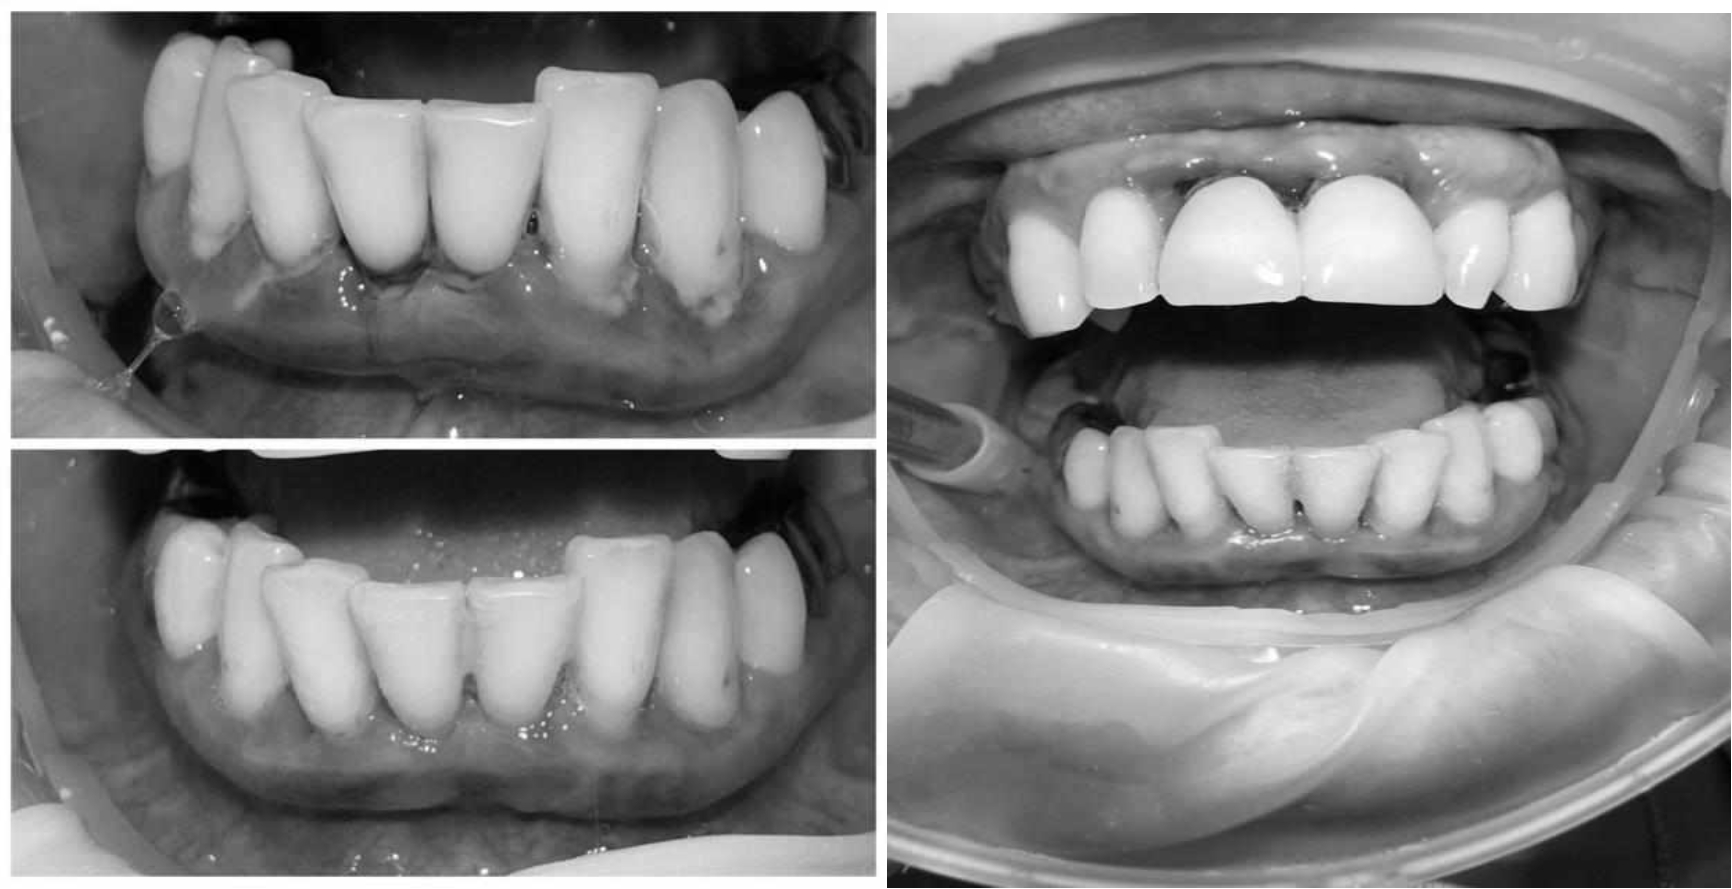

За пародонтологическим лечением обратилась женщина 61 года с жалобами на неприятный запах из полости рта, кровоточивость десен при чистке зубов, подвижность зубов, несостоятельность ортопедических конструкций.

Ранее у пародонтолога не наблюдалась. При осмотре выявлены: неудовлетворительная индивидуальная гигиена полости рта, пародонтальные карманы до 7 мм, обильная кровоточивость и гноетечение из пародонтальных карманов, подвижность зубов 4.2, 4.1, 3.1, 3.2 II степени, обильные над- и поддесневые зубные отложения (рис. 1). На ортопантомограме отмечается резорбция костной ткани до ½ длины корня, очаги остеопороза (рис. 2). Пациенту был поставлен диагноз хронический генерализованный пародонтит тяжелой степени тяжести. При осмотре была составлена пародонтограмма с использованием компьютерного зондирования (рис. 3).

Рис. 1. Внешний вид

Через 6 месяцев при осмотре выявлен удовлетворительный уровень индивидуальной гигиены, отсутствие участков кровоточивости и гноетечения (рис. 4), пародонтальные карманы уменьшились в размерах (рис. 5). Пациент отмечает значительные улучшения. После стабилизации пародонтологического статуса пациент направлен для дальнейшего ортопедического лечения.

Рис. 4. Динамика результата через 6 месяцев